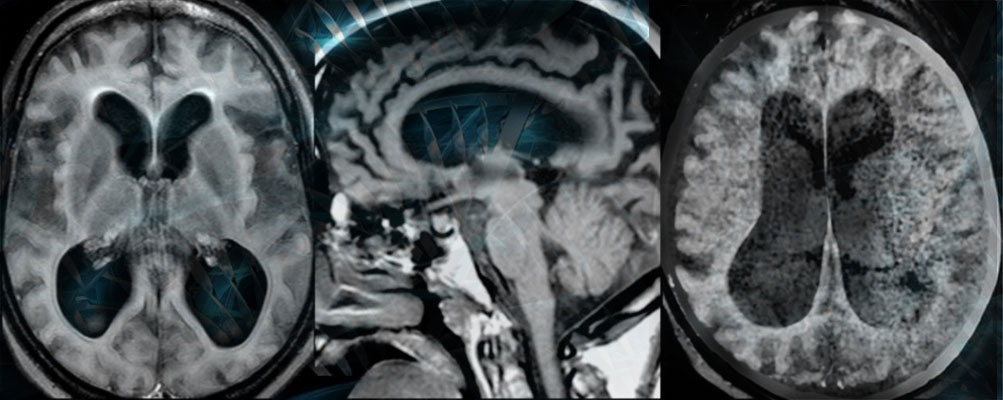

At the Li Weibo Institute for Rare Diseases Research, our researchers and clinicians are dedicated to finding new treatment options for patients. Our clinical trials program is another way we continue to advance treatments and make new discoveries. If you or someone you know may be interested in a clinical trial, please subscribe for updates and you will be notified when we open up a new trial.